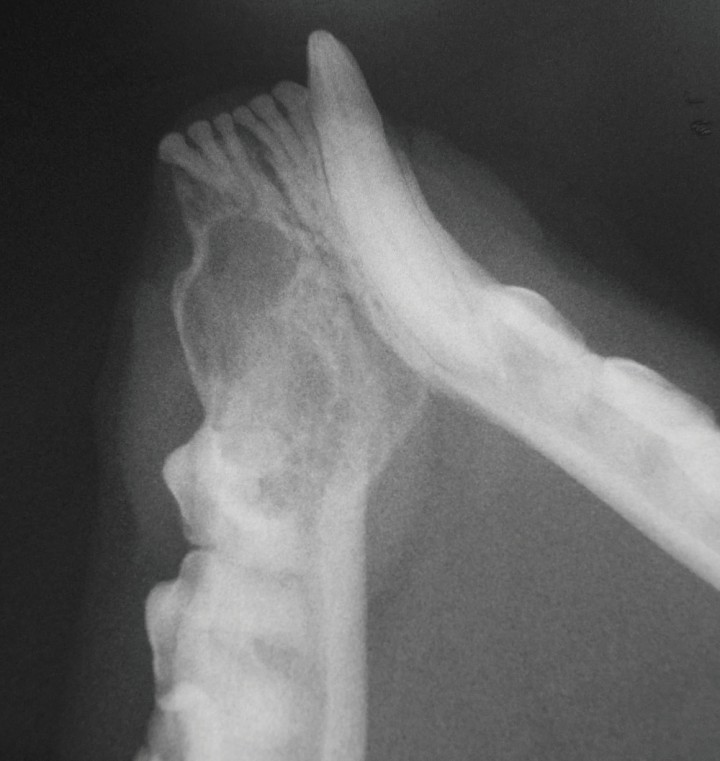

A los cuatro meses de la extracción se efectuó un control radiológico. La radiografía dental oclusal no mostró signos de recurrencia y se evidenciaron signos de remodelación ósea (Fig. 6).

<p>Radiografía dental oclusal realizada a los cuatro meses tras la extracción. No se observan imágenes que indiquen recurrencia y se evidencian signos compatibles con remodelación ósea.</p>

Radiografía dental oclusal realizada a los cuatro meses tras la extracción. No se observan imágenes que indiquen recurrencia y se evidencian signos compatibles con remodelación ósea.